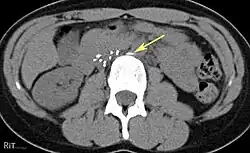

IVC filters are placed endovascularly, meaning that they are inserted via the blood vessels. Historically, IVC filters were placed surgically, but with modern filters that can be compressed into much thinner catheters, access to the venous system can be obtained via the femoral vein (the large vein in the groin), the internal jugular vein (the large vein in the neck) or the arm veins with one design. Choice of route depends mainly on the number and location of any blood clot within the venous system. To place the filter, a catheter is guided into the IVC using fluoroscopic guidance, then the filter is pushed through the catheter and deployed into the desired location, usually just below the junction of the IVC and the lowest renal vein.[44]

Review of prior cross-sectional imaging or a venogram of the IVC is performed before deploying the filter to assess for potential anatomic variations, thrombi within the IVC, or areas of stenoses, as well as to estimate the diameter of the IVC. Rarely, ultrasound-guided placement is preferred in the setting of contrast allergy, chronic kidney disease, and when patient immobility is desired. The size of the IVC may affect which filter is deployed, as some (such as the Birds Nest) are approved to accommodate larger cavae. There are situations where the filter is placed above the renal veins (e.g. pregnant patients or women of childbearing age, renal or gonadal vein thromboses, etc.). Also, if there is duplication of the IVC, the filter is placed above the confluence of the two IVCs [45] or a filter can be placed within each IVC.[46]